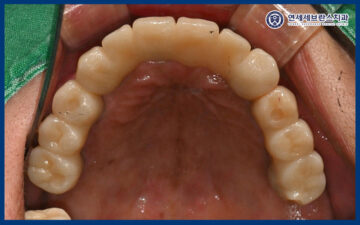

25.12.29

<보철 1차 세팅>

이렇게 제작된 보철을 맞춰보며

수정할 부분이 있는지 확인해 보고,

교합의 높이나 좌우 균형,

발음 시 불편감 여부 등을 함께

점검하는 과정을 거쳤습니다.

26.01.12

이후 최종적으로 전체적인 교합 상태와

보철물의 안정성을 다시 한 번 확인한 뒤

치료를 마무리하였습니다.

환자분께서는 치아가 하나도 없었는데

어금니가 다 생겨서 만족해 주셨습니다.